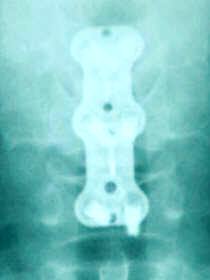

Discectomy of C5-6 and C6-7 with removal of the compressing fragments at the left foramen of C6-7. Insertion of Fidji cages 17 mm width 6.3 height and 12 mm depth was inserted to the C5-6 level with novabone. Another cage 17 mm width, 6.1 mm height and 12 mm depth was inserted with novabone to the C6-7 level. Using Trinica Zimmer miniplate 2 level 44 mm length was used to fuse C5-6-7. Image-intensifier was used at all stages of the operation.

Immediate postoperative X-ray 6 hours after surgery after ambulating.

Trinica Zimmer cervical miniplate